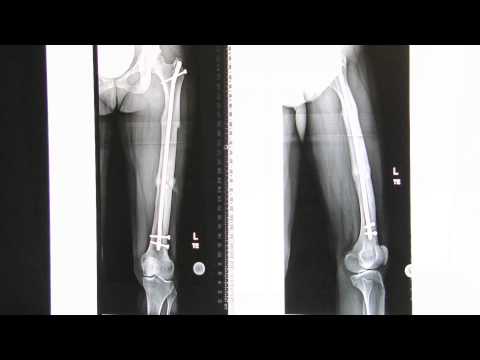

Limb Deformity Correction with Internal Fixation